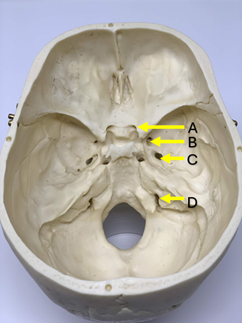

Q2. Through which of the following foramina does the nerve supplying the muscles of mastication pass?

- A

- B

- C

- D

Answer – C